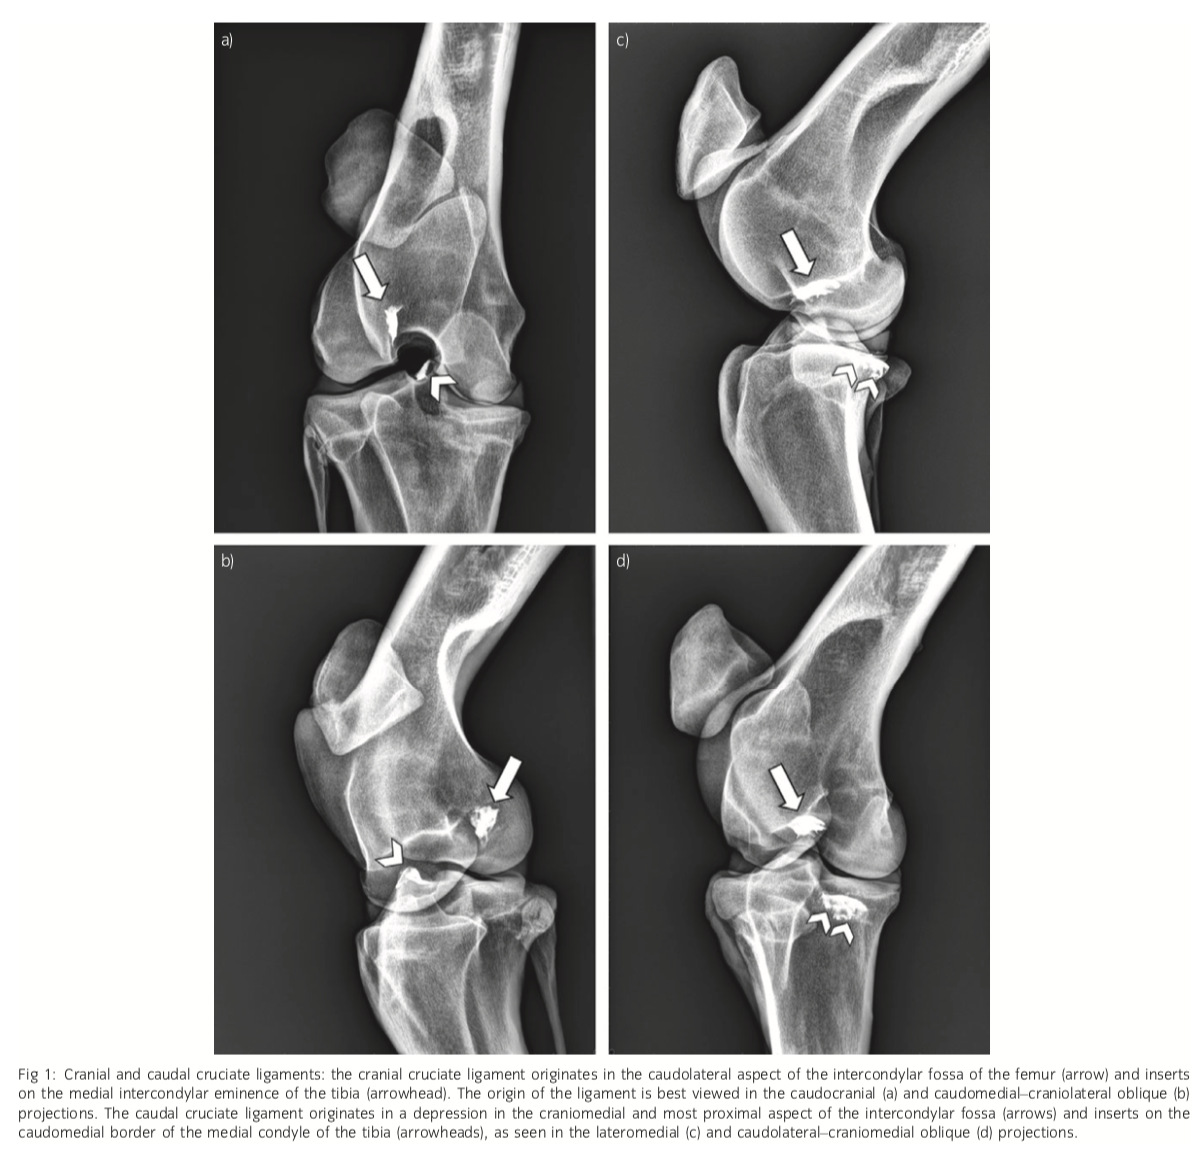

Cranial cruciate origin and insertion

Origin: caudolateral intercondylar fossa (10 o’clock position in the intercondylar fossa on CC rad

Insertion: Axial aspect of the MICET

Caudal cruciate origin and insertion

Origin: craniomedial intercondylar fossa

Insertion: caudomedial border of the medial tibil condyle

Remember named as per cr/cau insertions on the tibia